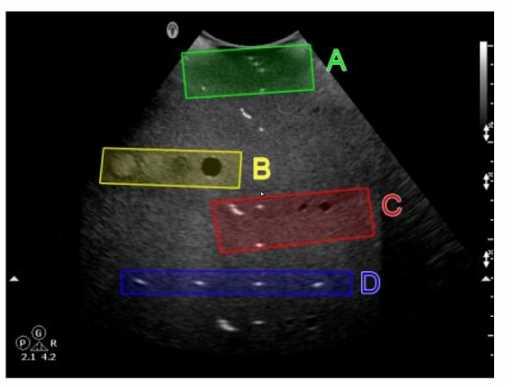

Which target group is used to evaluate transverse distance measurement accuracy in this tissue- mimicking phantom image?

Answer(s): D

In the tissue-mimicking phantom image, Option D (blue box) is used to evaluate transverse distance measurement accuracy. Phantoms are used to simulate human tissue and provide a standardized way to test the accuracy and precision of ultrasound machines. Transverse distance measurement accuracy is assessed by measuring known distances between targets in the phantom. The blue box (Option D) typically contains targets positioned to specifically test the accuracy of transverse measurements, ensuring that the ultrasound system provides reliable and precise distance readings.